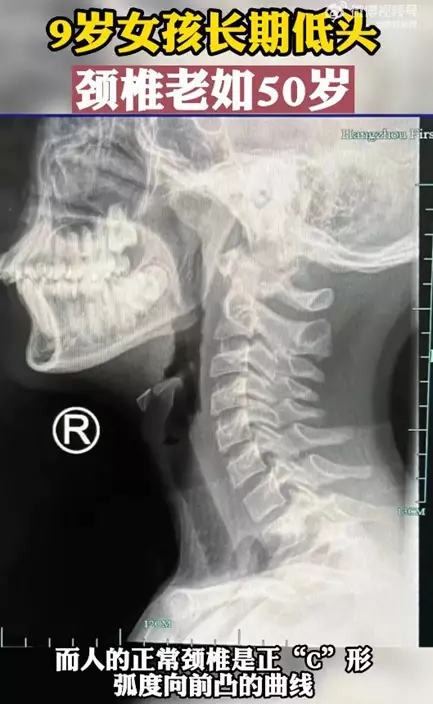

浙江杭州一名9歲女孩銘銘最近常出現脖子酸痛、手指發麻等症狀。醫生檢查後發現她的頸椎已老化如50歲長者,人的正常頸椎是呈正「C」形,而女童的頸椎弧度往反方向彎曲變成「一條直線」。原來,銘銘除了平時寫功課外,還沉迷於玩手機,經常一玩就是幾個小時,因此導致了嚴重的脊椎病,醫生藉此提醒各位家長,一定要關注子女的脊椎健康問題。